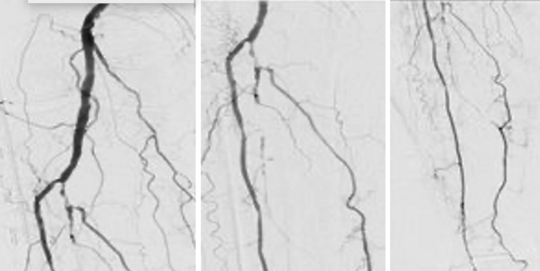

76-jährige Dame mit peripherer arterieller Verschlusskrankheit PAVK und Ruheschmerz (Stadium Fontaine 4), Katheter-Angiographie des Unterschenkels

Die Gefäßdarstellung zeigt komplexe Verschlüsse der direkten Fortsetzung der Arterie, die sich im Bereich der Kniekehle befindet, eine der beiden Hauptarterien des Unterschenkels und der lateralen (äußeren) Seite des Unterschenkels und des Fußes.

Eine Passage der Verschlüsse auf direktem Weg von vorwärts gerichtet ist nicht möglich. Daher erfolgt die rückwärts gerichtete Sondierung über ein Kollateralgefäß.

Danach gelingt die rückwärts gerichtete Passage der Verschlüsse.